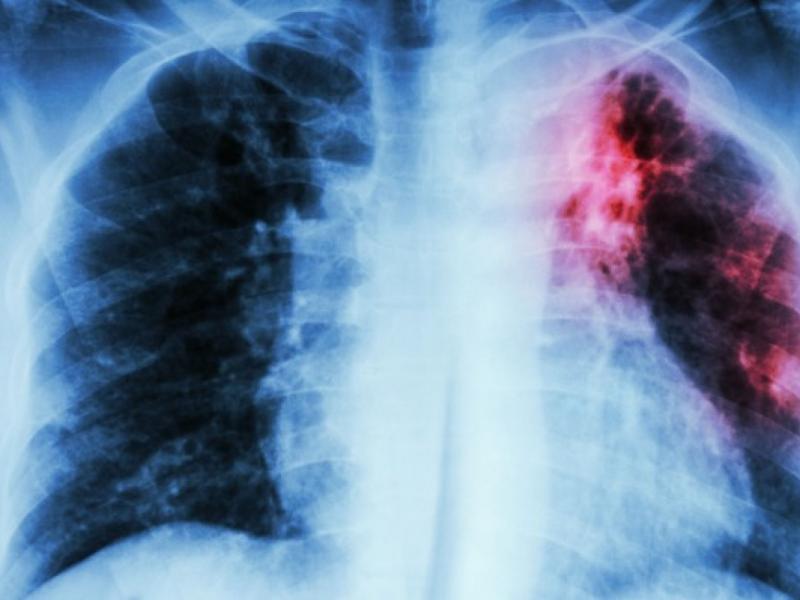

14.12.2019 - 08:56 Πνευμονολόγος προειδοποιεί: Η φυματίωση δεν είχε εξαλειφθεί ποτέ στην Ελλάδα «Η φυματίωση δεν είχε εξαλειφθεί ποτέ, ούτε παγκοσμίως, ούτε στην Ελλάδα. Με την ευρεία χρήση συνδυασμού αποτελεσματικών φαρμάκων, την δεκαετία του... ΕΠΙΣΤΗΜΗ Πνευμονολόγος προειδοποιεί: Η φυματίωση δεν είχε εξαλειφθεί ποτέ στην Ελλάδα